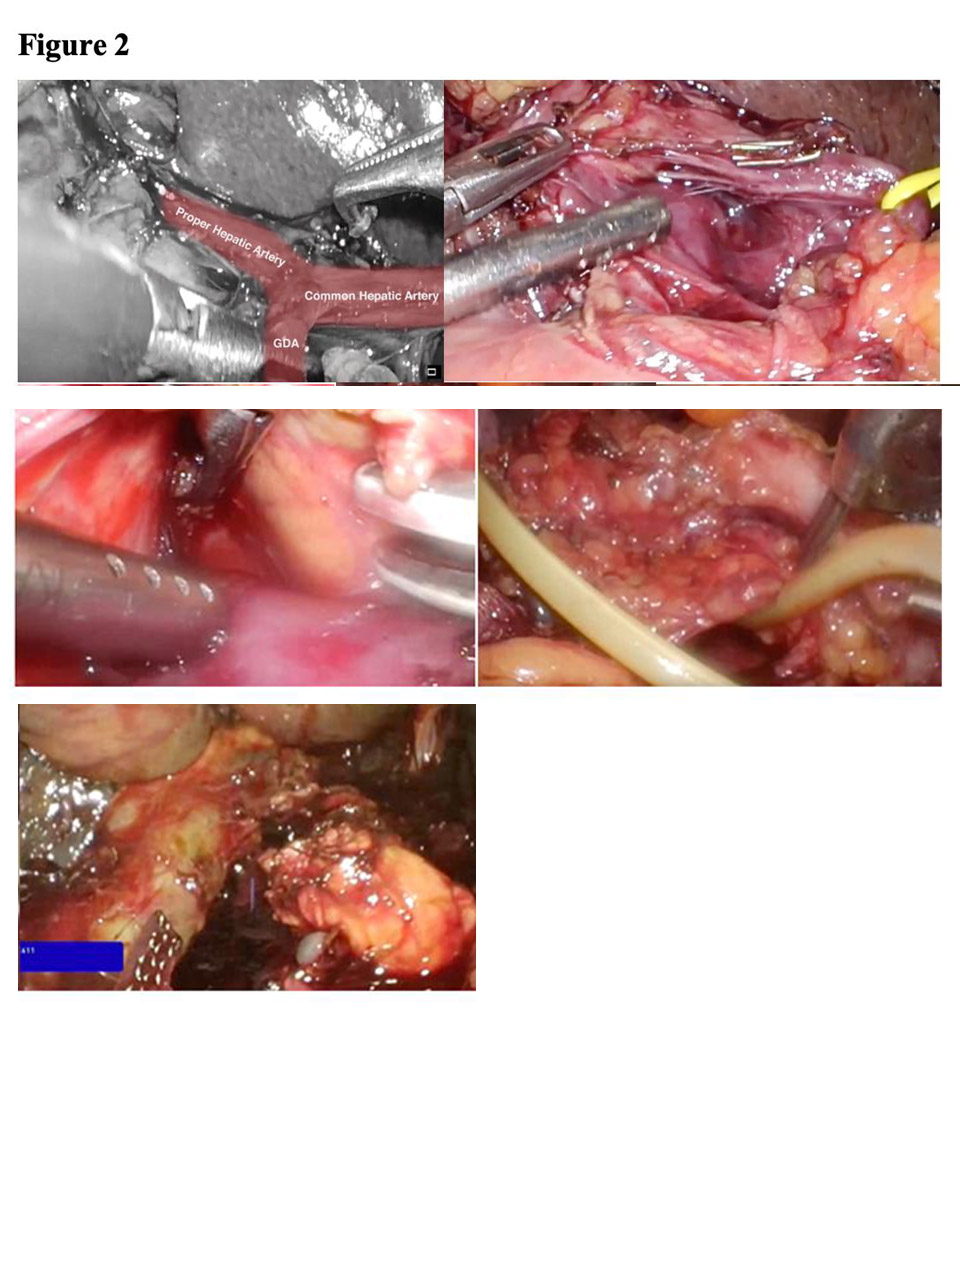

Pancreatoduodenectomy

Diagram of Classical WhipplePancreatoduodenectomy is a formidable operation It involves removal of the head and uncinate process of the pancreas, the duodenum, the common bile duct and the gallbladder, with reconstruction by anastomosing the pancreatic remnant to the proximal jejunum or stomach, common hepatic duct to proximal jejunum and stomach or proximal duodenum to the jejunum.

The classical operation is called the Whipple resection, which includes removal of the distal stomach (gastric antrum and pylorus as well). These days we usually preserve the stomach and pylorus, the operation being called the pylorus-preserving proximal pancreatoduodenectomy (PPPPD).